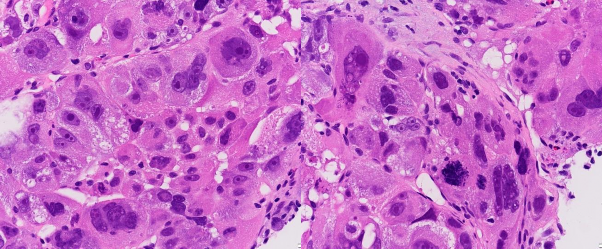

B |

Ảnh 3.6. UTBMTBG thể đa hình với các tế bào u đa dạng về kích thước, có cả tế bào khổng lồ, nhân quái (A, B) (HE x 400, mã số:1107)